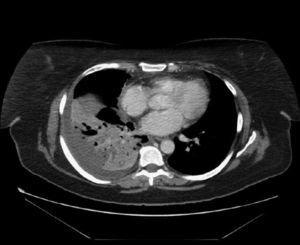

Observación clínicaCaso 1Mujer de 49 años, diagnosticada de artritis reumatoide (AR) a los 40, en tratamiento con metotrexato y esteroides a dosis bajas y, desde febrero de 2006, con adalimumab por vía subcutánea (40mg cada 2 semanas). La AR se hallaba en remisión. Presentaba una prueba de la tuberculina y un efecto de refuerzo negativos. Se había incrementado la dosis de esteroides a 10mg de prednisona ante la presencia de un cuadro indicativo de eritema nudoso 3 meses antes. Acudió a urgencias por cuadro de tos, sudoración profusa y fiebre, que alcanzó 38°C, de 4 semanas de evolución. Se estableció el diagnóstico de neumonía de la comunidad y recibió tratamiento con amoxicilina-ácido clavulánico, sin mejoría, por lo que acudió de nuevo a urgencias. En la radiografía de tórax se apreció una consolidación en el lóbulo inferior derecho. La tomografía computarizada (TAC) mostró una consolidación parenquimatosa en dicho lóbulo (fig. 1). Se inició tratamiento con levofloxacino, con parcial mejoría clínica y radiológica. Al séptimo día reapareció la fiebre. Mediante la inducción de esputo se obtuvo una muestra donde se detectaron bacilos ácido-alcohol resistentes y en la que el cultivo para Mycobacterium tuberculosis complex fue positivo. Se instauró tratamiento con isoniacida, rifampicina y piracinamida. La paciente reingresó al cabo de una semana por vómitos, dolor abdominal e ictericia; la bioquímica hepática mostró bilirrubina de 7,3U/l, a expensas de bilirrubina directa; aspartato aminotransferasa de 146U/l, alanina aminotransferasa de 158U/l, fosfatasa alcalina de 515U/l y gammaglutamil transpeptidasa de 136U/l. Se interrumpió el tratamiento tuberculostático. A los 11 días del ingreso se reinstauraron progresivamente la isoniacida y la rifampicina, y se inició estreptomicina, hasta que las pruebas de sensibilidad permitieron retirarla. La evolución posterior de la paciente fue buena y su AR está en remisión.